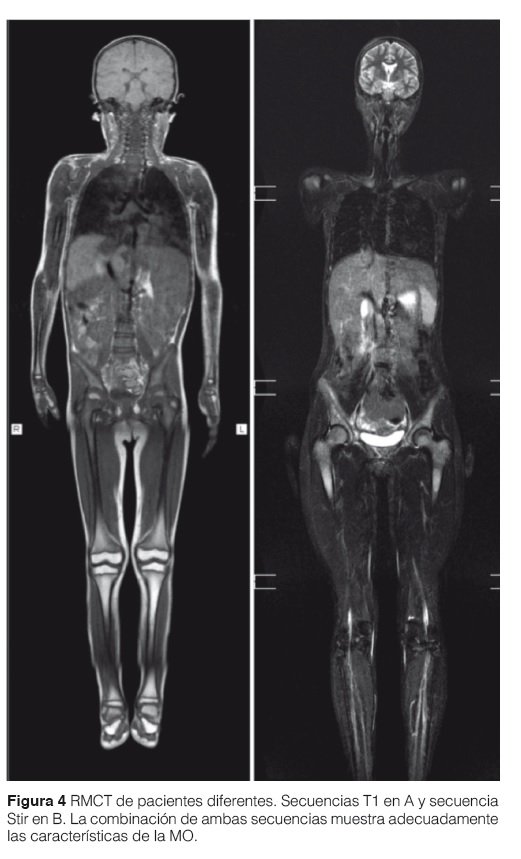

Para la evaluación de la médula ósea utilizamos Resonancia Magnética Corporal Total (Whole Body) en equipos de alto campo (1,5 o 3 Tesla). Las secuencias utilizadas son SE T1 y Stir en cuerpo entero y columna y FSE T2 de fémures. No utilizamos contraste endovenoso (Fig.4).

La combinación de secuencias SE T1 y Stir permite una exacta valoración de la médula ósea. El reemplazo de la médula ósea habitual por células de Gaucher (hipointenso) se ve reflejado claramente en las secuencias T1 y T2 sin saturación de grasa gracias a su calidad anatómica y alto contraste con la grasa hiperintensa normal de la MO grasa o amarilla. En secuencias SE T1 comprobamos el grado de infiltración, tipo de infiltración (homogéneo o heterogéneo) y el daño estructural óseo. En secuencias STIR se evalúa también la infiltración de la MO y pero principalmente y gracias a su gran sensibilidad al edema óseo (hiperintenso en Stir) se evalúa la presencia de lesiones agudas, destacándose las crisis óseas, los infartos, la necrosis avascular y las fracturas (Fig. 5).